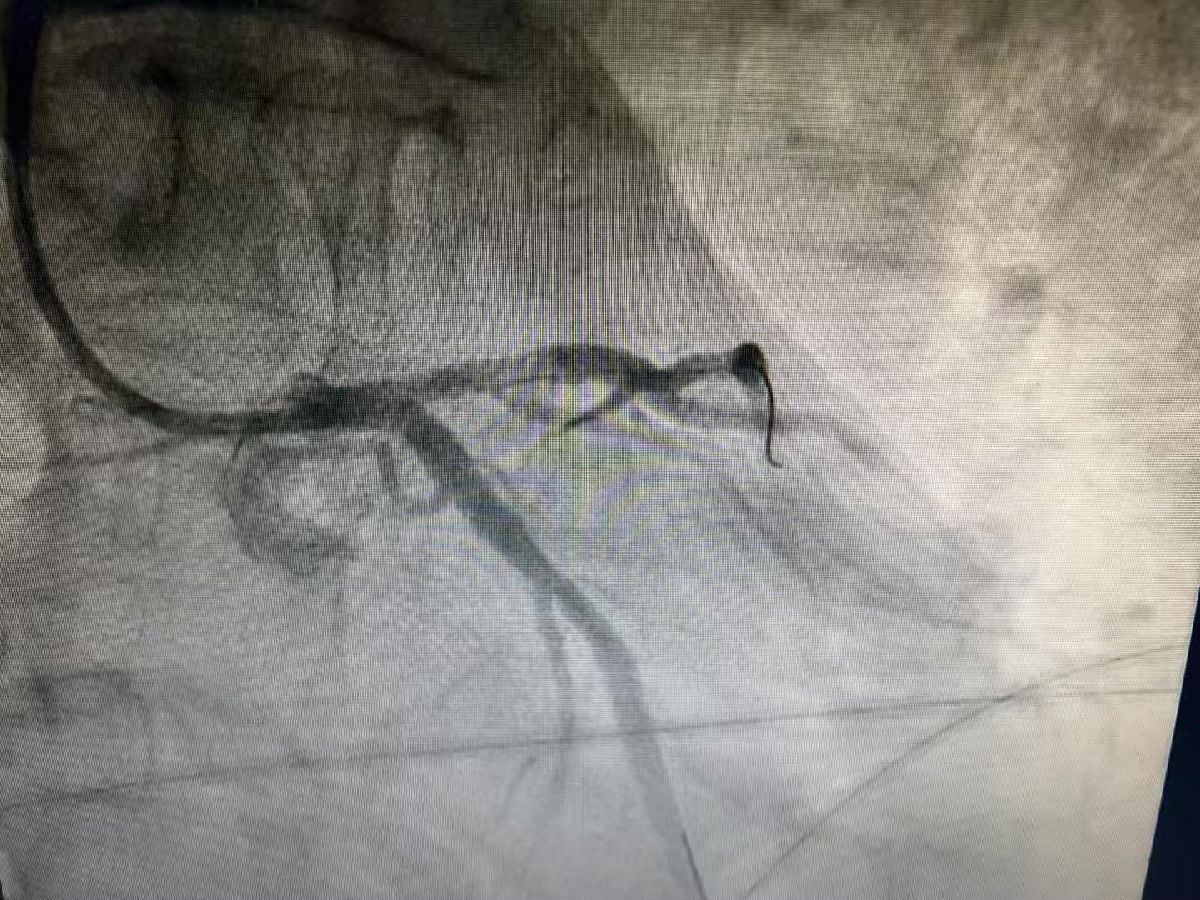

重获新生,一面锦旗诉真情

经过CCU(心脏重症监护室)一周的精心治疗和护理,王师傅康复出院。一个月后,他返院复查,结果令人欣喜,复查造影显示,血管内的血栓已完全消失。近日,王师傅特意带着锦旗来到门诊,激动地握住医生的手:“谢谢,太谢谢你们了!是你们把我从鬼门关拉了回来,给了我第二次生命!”